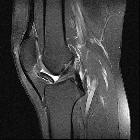

MRI

Features include

-

T1

- mass in the Hoffa fat pad

- generally low signal

- isointense to muscle

- some dark areas signifying calcification

- T2: high signal in the cartilaginous components

- PD: as above with T1, plus high intensity signal areas corresponding to medullary bone

- GRE: prominent signal voids within a nodular mass